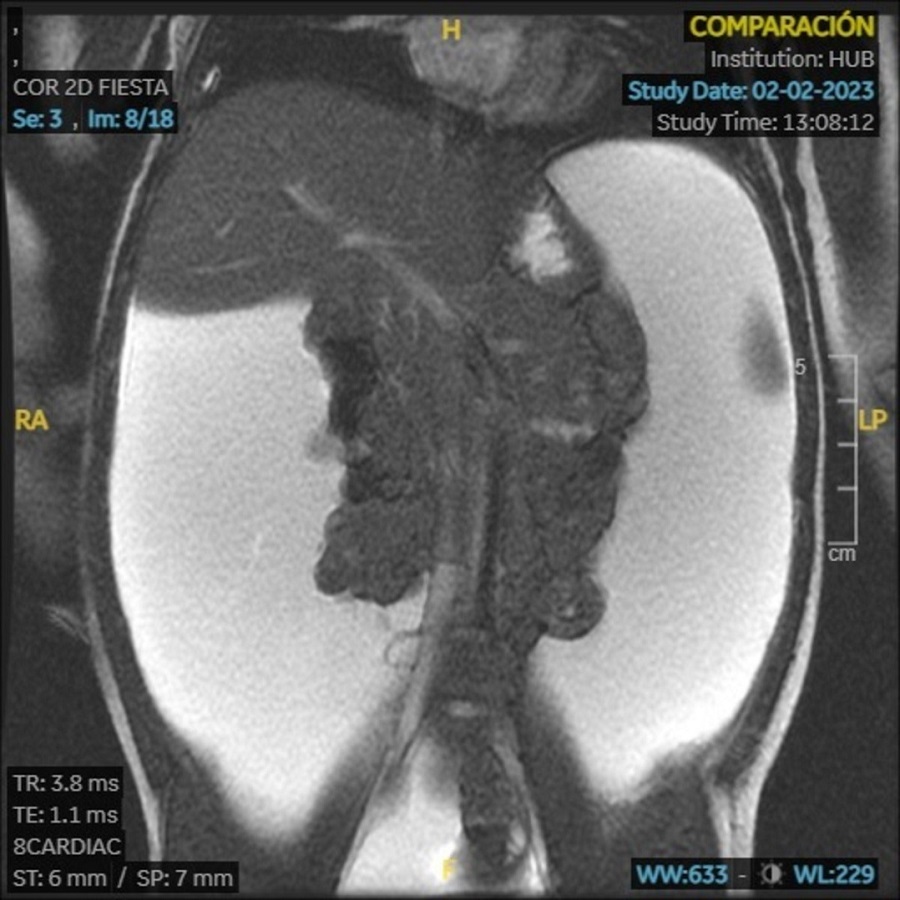

En la ecografía Doppler se observa gran cantidad de líquido libre peritoneal con ecos difusos en su interior y algunos tabiques. Se realiza resonancia magnética (RM) con los hallazgos que se muestran en las Figuras 1 y 2.

Figura 1. RM abdominal. Corte coronal. Lesión quística desde mesogastrio hasta pelvis (33 x 12 x 10 cm) que desplaza las asas del intestino delgado y presenta tabiques en el margen posterior derecho. Se muestra hiperintensa en T1.